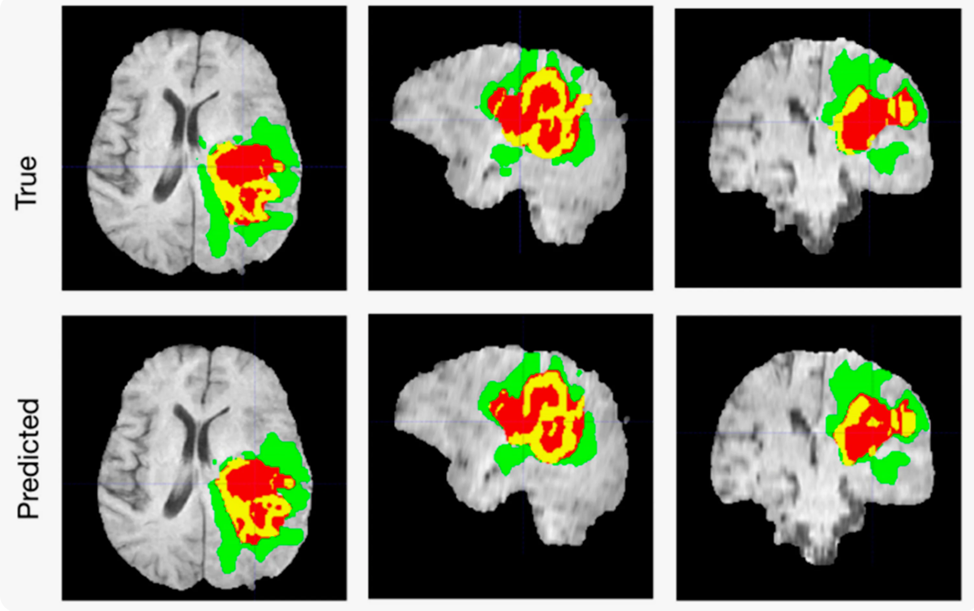

Еще одна интересная и очень нужная тема, это обработка медицинских изображений. Создание модели для анализа медицинских изображений в целях диагностики, например, обнаружения опухолей на МРТ‑снимках, является очень важной областью применением компьютерного зрения в здравоохранении. Приведенный ниже проект включает в себя обучение модели глубокого обучения для точного определения и классификации заболеваний на основе изображений.

Здесь нам потребуются библиотеки TensorFlow или PyTorch. В примере ниже мы будем использовать TensorFlow. Далее нам необходимо получить данные медицинских изображений. Это достаточно специфичная область данных, но и здесь есть общедоступные наборы данных, например, BraTS, для сегментации опухолей головного мозга.